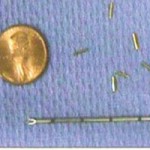

Προϋπόθεση είναι η τοποθέτηση εντός του προστάτη αδένος, τριών έως τεσσάρων "δεικτών αναφοράς" (3 – 4 fiducials), οι οποίοι εντοπίζονται από το σύστημα κεντροθετήσεως, και ανάλογα με τις μικρομετακινήσεις του στόχου, δίδεται εντολή και ο ρομποτικός βραχίονας διορθώνει την απόκλιση της δέσμης από εκατοστά έως δέκατα του χιλιοστού.

Η τοποθέτηση των "δεικτών αναφοράς" (κομμάτια σύρματος καθαρού χρυσού μήκους πέντε και πάχους 0,8 χιλιοστών (5 Χ 0,8 mm) εμφυτεύονται στον προστάτη με λεπτή βελόνα (18 G) υπό ενδορθική υπερηχογραφική καθοδήγηση.

Οι «δείκτες – fiducials» είναι μικρά κυλινδρικά κομμάτια καθαρού χρυσού (Au 99,9 %) χωρίς ίχνος ακτινοβολίας, μήκους 5 χιλιοστών που εμφυτεύονται μέσα στον προστάτη αδένα όπου θα γίνει και η θεραπεία με CyberKnife®.

Με τον τρόπο αυτό, το ψηφιακό σύστημα αναγνωρίζει τη σωστή θέση του στόχου ανά πάσα στιγμή και σε περίπτωση κινήσεώς του, ο ρομποτικός βραχίονας να κάνει τις ανάλογες διορθώσεις ώστε να υπάρχει πάντα απόλυτη ευστοχία των δεσμών ακτινοβολίας που θα στείλει το σύστημα.

Πώς τοποθετούνται;

Οι «δείκτες – fiducials» είναι τοποθετημένοι μέσα σε λεπτές ειδικές βελόνες (δεν διαφέρουν σε διάμετρο με αυτές των αιμοληψιών) και εμφυτεύονται στο προστάτη υπό καθοδήγηση διορθικού υπερηχογράφου από ειδικό Ουρολόγο ή Ακτινοθεραπευτή Ογκολόγο. Πριν εμφυτευτούν, γίνεται κάποια προετοιμασία του εντέρου, ίδια ή παρόμοια με αυτή που έγινε προ της βιοψίας.

Πότε πρέπει να εμφυτευτούν;

Η εμφύτευση των «δεικτών – fiducials» γίνεται 5 – 7 ημέρες πριν τις μετρήσεις και την προετοιμασία του ασθενούς για θεραπεία. Αυτό γίνεται ώστε ο οργανισμός να έχει χρόνο να σταθεροποιήσει τη θέση τους και να θεωρούνται πλέον ακίνητα σημεία ως προς τον στόχο που θα επικεντρώσουμε τη θεραπεία.

Υπάρχουν παρενέργειες από την εμφύτευση;

Κάθε επεμβατική πράξη έχει κινδύνους και πιθανές παρενέργειες. Στη περίπτωση όμως των εμφυτεύσεων στον προστάτη αδένα οι πιθανότητες είναι μηδαμινές για κάτι περισσότερο από μία τοπική λοίμωξη λόγω κακής προετοιμασίας του εντέρου. Η πιθανότητα αυτή μηδενίζεται με τη χορήγηση ολιγοήμερης χορηγήσεως αντιβιοτικού.

Για πόσο διάστημα μένουν μέσα στο σώμα;

Οι «δείκτες – fiducials» μένουν μέσα στο σώμα για πάντα. Το μικρό τους μέγεθος καθώς και η κατασκευή τους από καθαρό χρυσό τα κάνει τελείως αποδεκτά από τους ιστούς και δεν δημιουργείται καμία παρενέργεια ή αντίδραση. Μάλιστα ο ασθενής μπορεί να υποβληθεί σε οποιαδήποτε εξέταση (Μαγνητική τομογραφία, Σπινθηρογράφημα, Υπερηχογράφημα κλπ) χωρίς πρόβλημα. Όμως στις Ακτινογραφίες της περιοχής, θα εμφανίζονται σαν μικρά μεταλλικά σημάδια, τα οποία εύκολα αναγνωρίζει ο Ακτινοδιαγνωστής και δεν του δημιουργούν διαγνωστικό πρόβλημα.